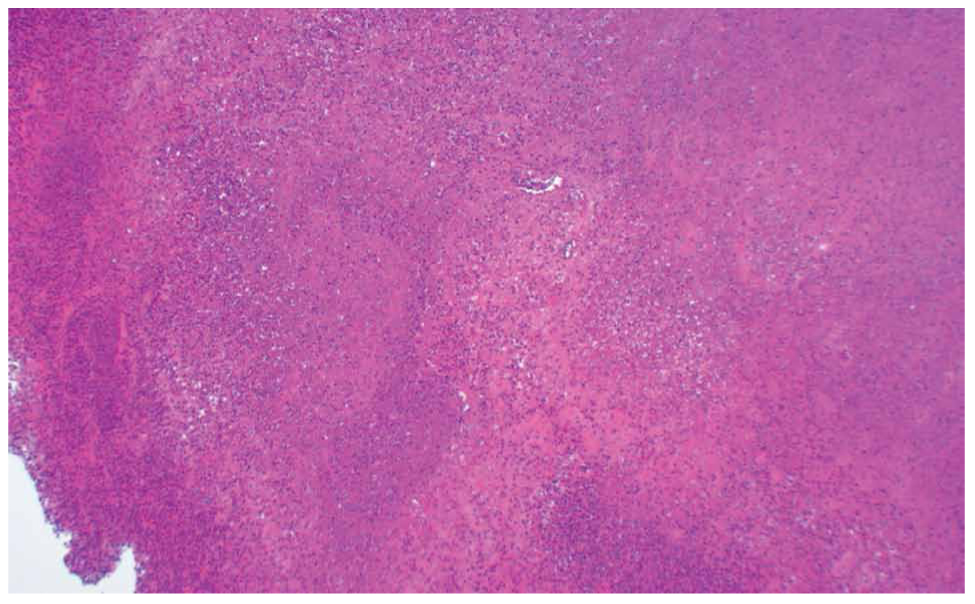

Two main histological subtypes exist: necrotizing and non-necrotizing granulomas [4]. Necrotizing granulomas have a necrotic focus surrounded by a rim of chronic inflammatory cells, including epithelioid macrophages [5] (Figure 1, 2). Although it is not a specific pathological finding, histologic identification of granulomatous inflammation is a useful predictor of diagnostic etiology and can lead to a definitive diagnosis with the aid of ancillary testing, such as special stains and molecular diagnostics. This is because the specific histologic patterns of the granuloma (e.g., foreign-body, necrotizing, non-necrotizing, suppurative, etc.) can help narrow the clinical differential diagnosis when considered alongside the clinical context (Figure 3, 4).

Figure 1. A 67-year-old patient with necrotic granulomatous lymphadenitis (x100).

Figure 2. Necrotic areas surrounded by a rim of epithelioid histiocytes and lymphocytes in the sample of the lymph node (x200).